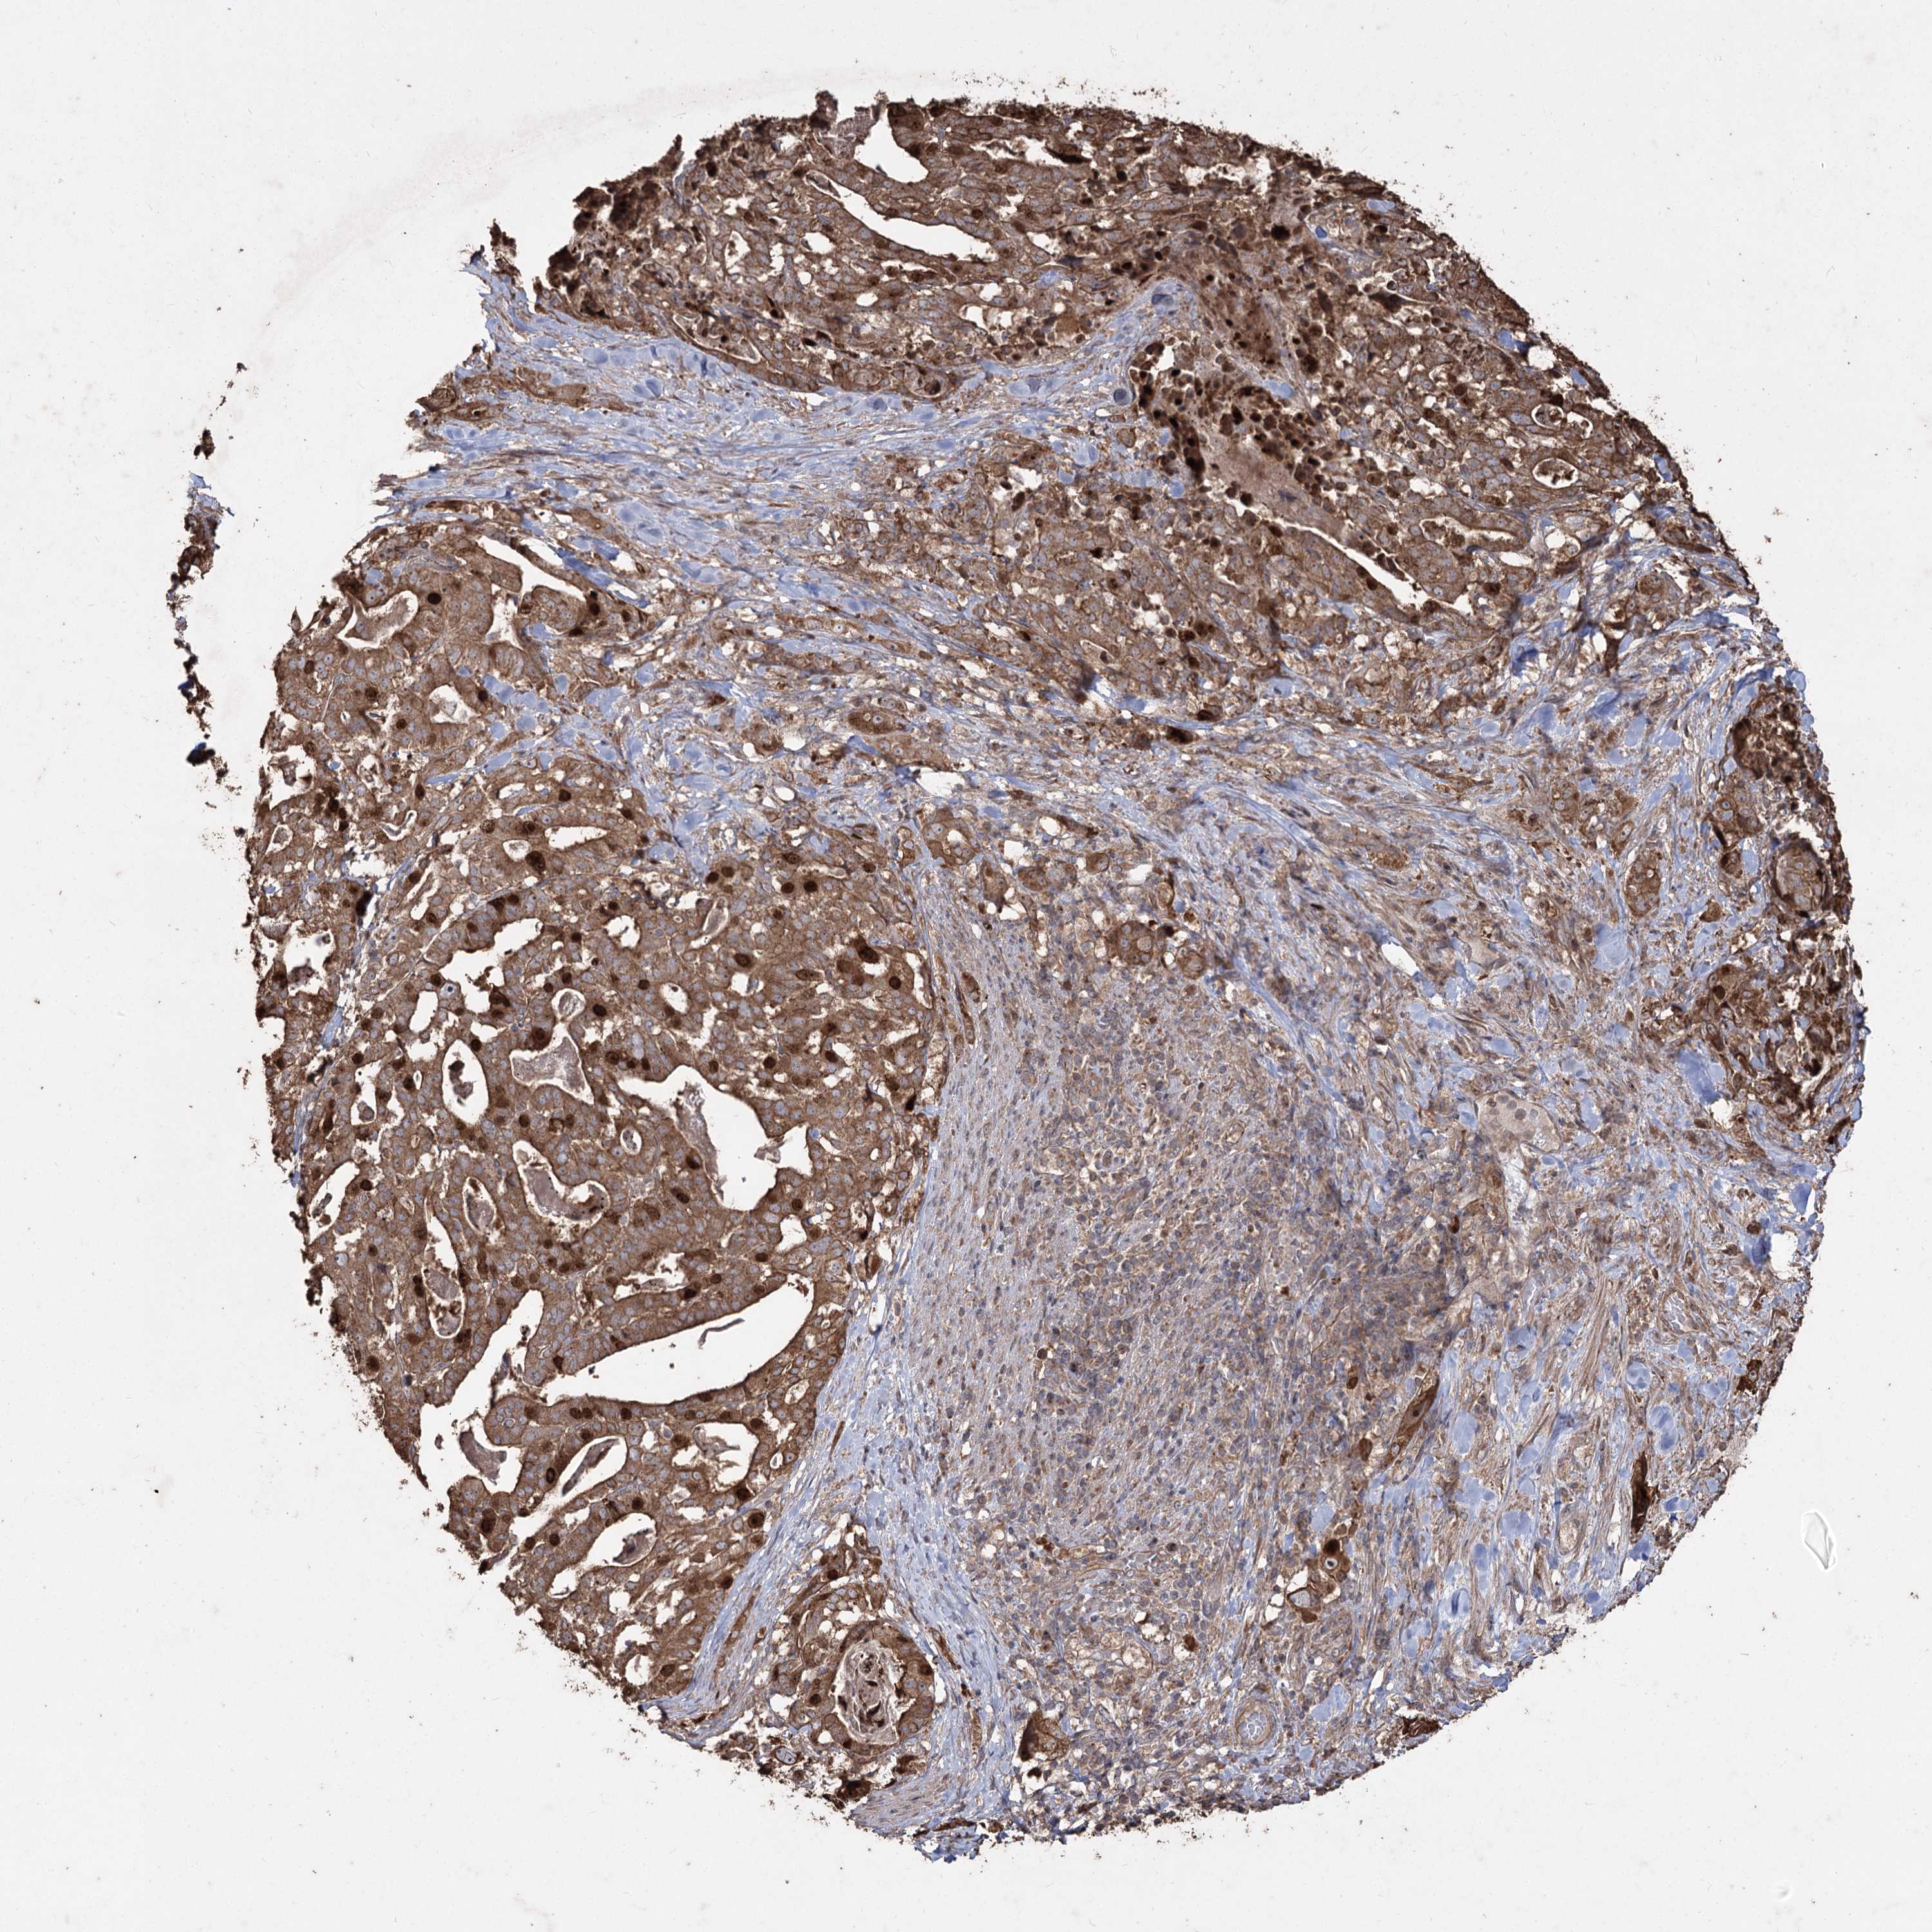

STOMACH CANCER - Protein expressioni

A mouse-over function shows sample information and annotation data. Click on an image to view it in a full screen mode. Samples can be filtered based on level of antibody staining by selecting one or several of the following categories: high, medium, low and not detected. The assay and annotation is described here.

Antibody stainingi

Antibody staining in the annotated cell types in the current human tissue is reported as not detected, low, medium, or high, based on conventional immunohistochemistry profiling in selected tissues. This score is based on the combination of the staining intensity and fraction of stained cells.

Each image is clickable and will lead to virtual microscopy that enables deeper exploration of all samples and also displays staining intensity scores, fraction scores and subcellular localization as well as patient and tissue information for each sample.

Antibody HPA034521

Antibody HPA048816

Staining

High

Medium

Low

Not detected

Intensity

Strong

Moderate

Weak

Negative

Quantity

>75%

75%-25%

<25%

None

Location

Nuclear

Cytoplasmic/membranous

Cytoplasmic/membranous,nuclear

Adenocarcinoma, NOS

Adenocarcinoma, High grade